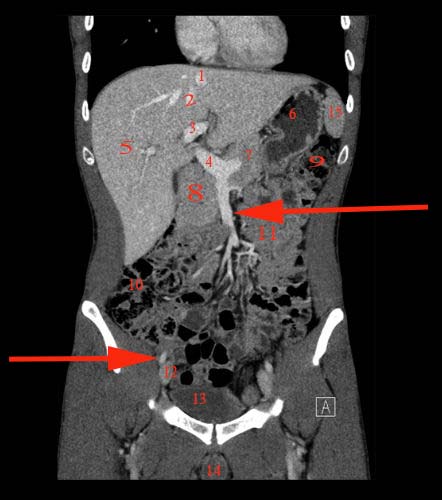

Abdomen coronal IQ test